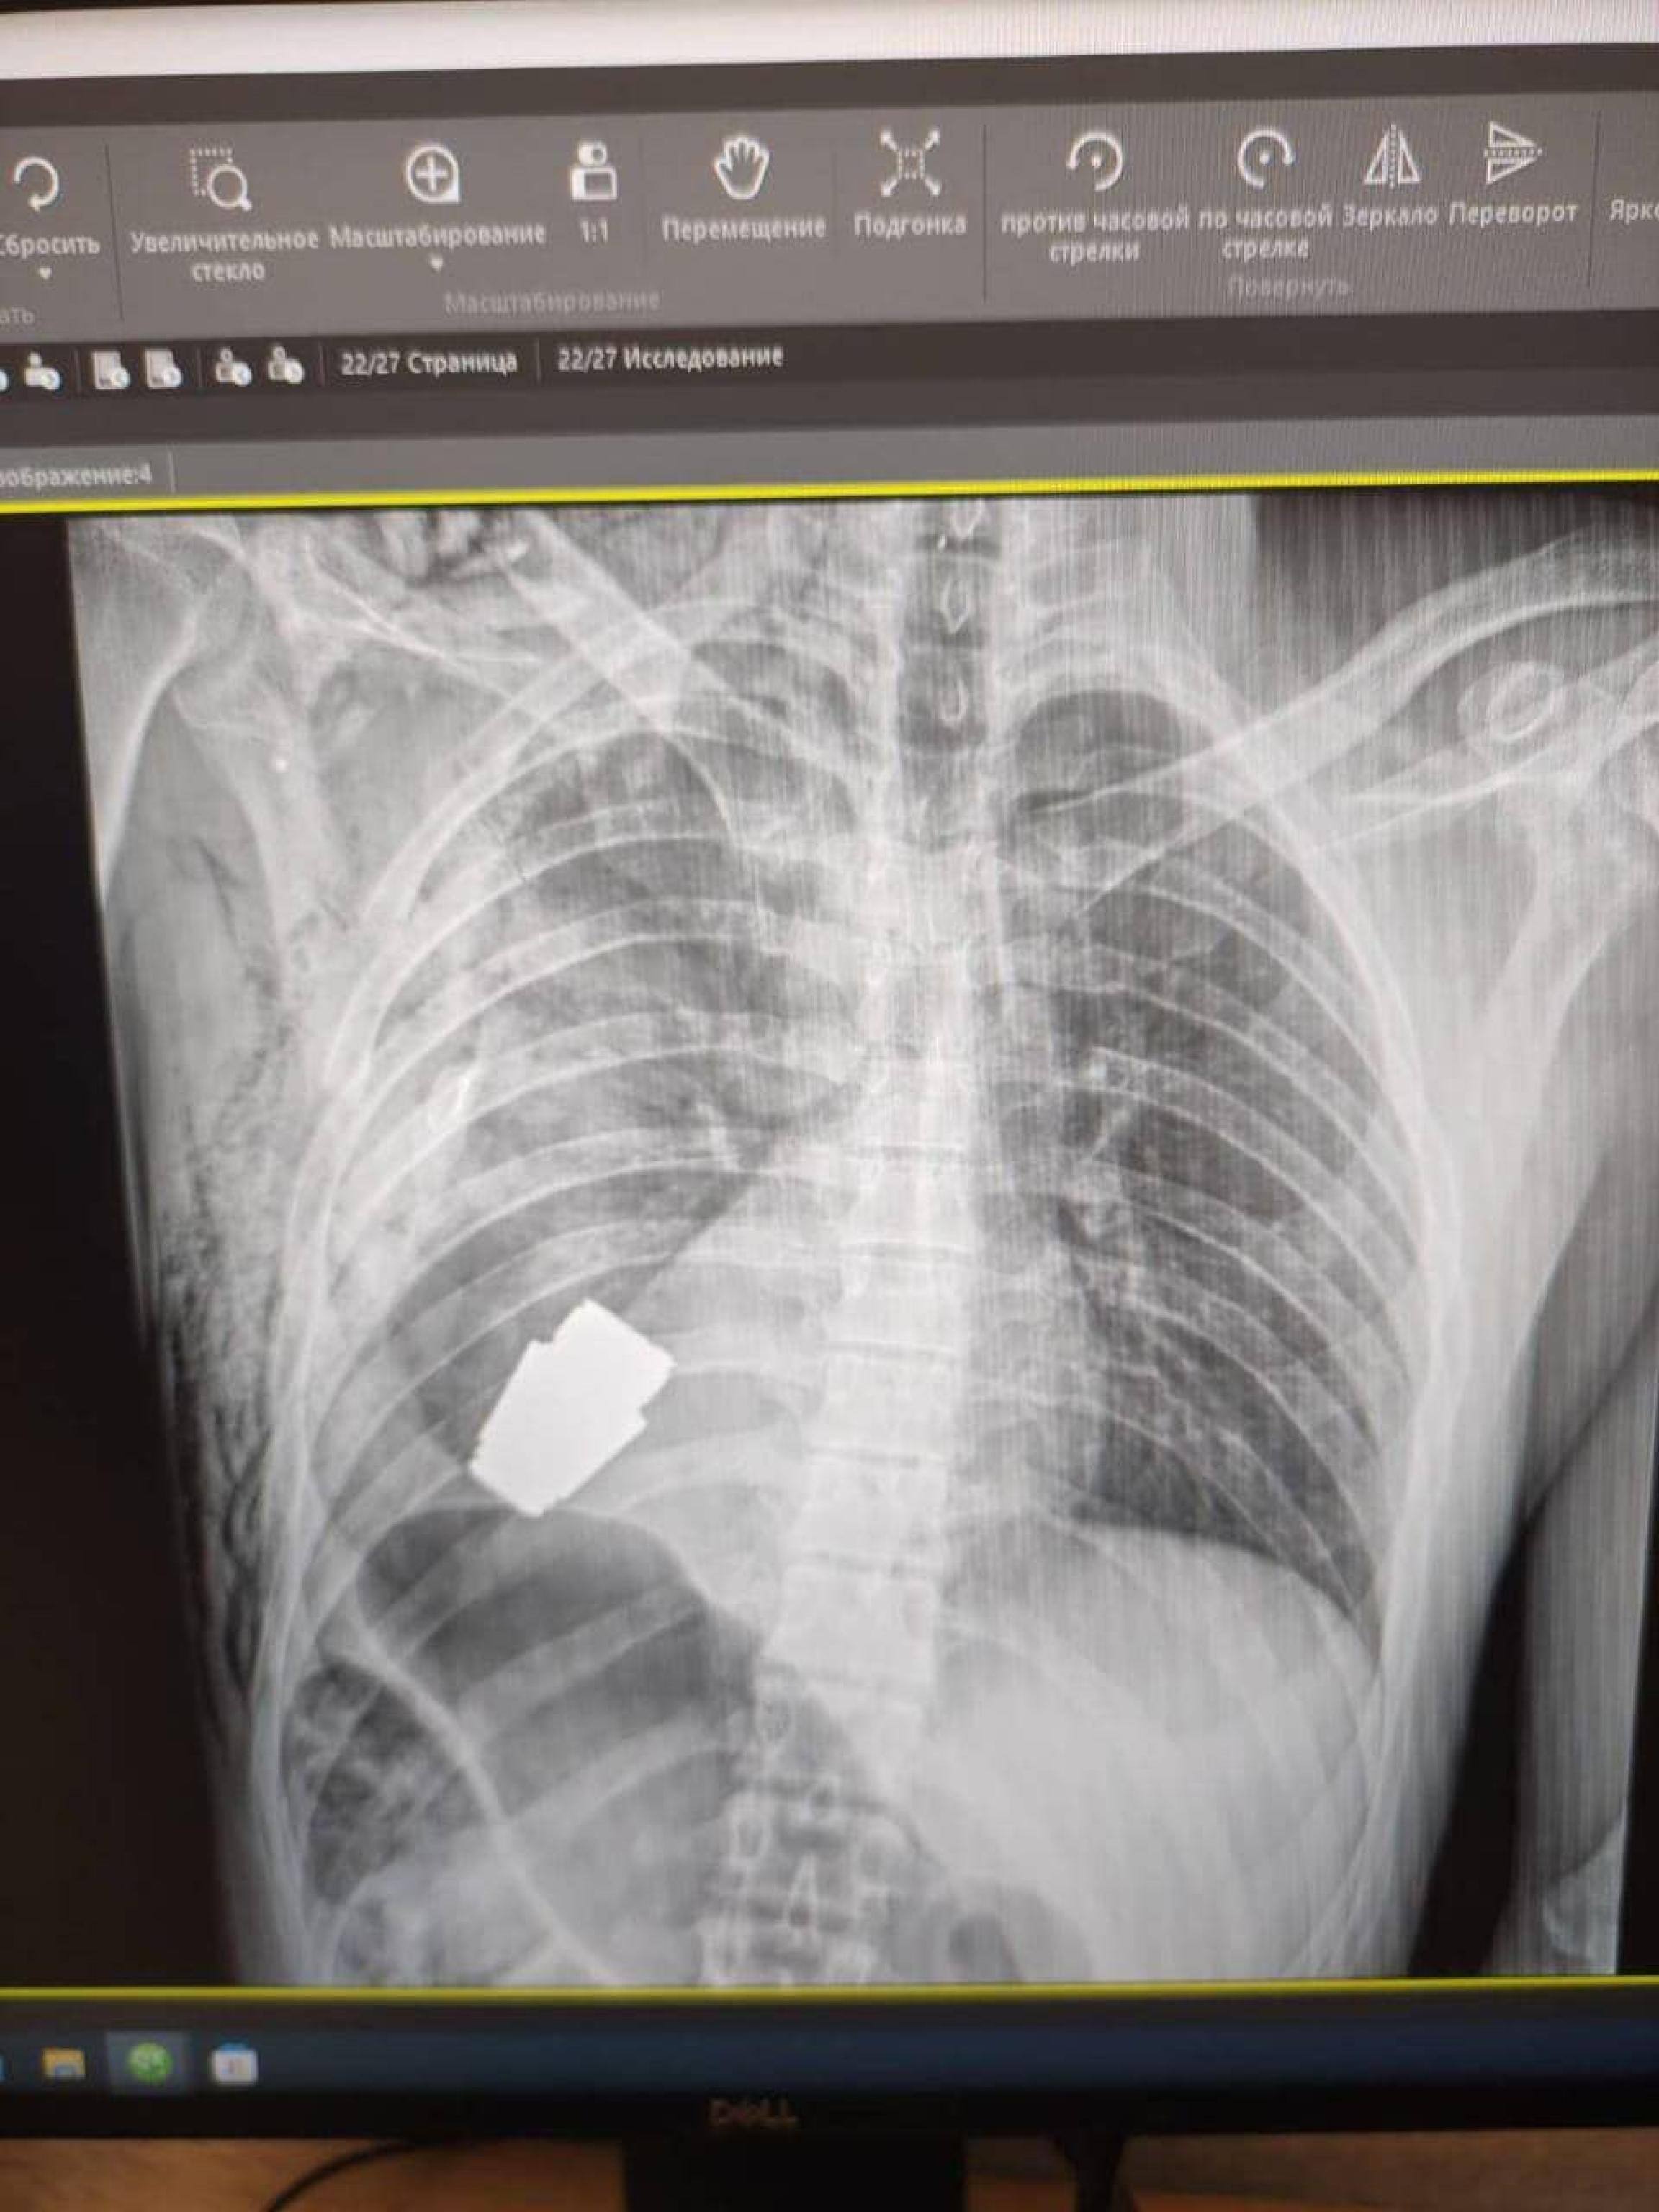

Una granata inesplosa è stata rimossa dal torace di un soldato ucraino durante un intervento chirurgico unico nel suo genere e destinato  a entrare nei libri di medicina. A raccontare l'operazione medica è stata la vice ministra della Difesa ucraina, Hanna Maliar. "I medici militari hanno condotto un'operazione per rimuovere una granata VOG, che non si è rotta, dal corpo del soldato", ha scritto in un post su Facebook. La vice ministra ha postato l'immagine di una radiografia in cui si vede l'ordigno all'interno del corpo del soldato e una foto di un chirurgo che osserva la granata dopo l'intervento (GUERRA UCRAINA-RUSSIA, SEGUI GLI AGGIORNAMENTI IN TEMPO REALE).

La parte inesplosa della granata si trovava sotto il cuore del militare ferito, ha precisato Gerashchenko. è stata eseguita senza utilizzare l'elettrocoagulazione (un metodo per controllare le emorragie durante gli interventi chirurgici) perché "la granata poteva esplodere in qualsiasi momento", ha sottolineato Maliar aggiungendo che due genieri erano presenti durante l'intervento per assicurati che fosse condotto in sicurezza. Una squadra di genieri ha in seguito neutralizzato l'ordigno, ha detto il consigliere ministeriale per gli affari interni dell'Ucraina, Anton Gerashchenko, definendo l'intervento come uno di quelli che "entreranno nei libri di testo di medicina". La parte inesplosa della granata si trovava sotto il cuore del militare ferito, ha precisato Gerashchenko.

Una granata inesplosa è stata rimossa dal torace di un soldato ucraino in un intervento chirurgico, secondo un alto funzionario di Kiev, unico nel suo genere: lo ha reso noto la vice ministra della Difesa ucraina, Hanna Maliar. "I medici militari hanno condotto un'operazione per rimuovere una granata VOG, che non si è rotta, dal corpo del soldato", ha scritto Maliar in un post su Facebook, come riporta il Guardian. La vice ministra ha postato l'immagine di una radiografia in cui si vede l'ordigno all'interno del corpo del soldato e una foto di un chirurgo che osserva la granata dopo l'intervento. L'operazione è stata eseguita senza utilizzare l'elettrocoagulazione (un metodo per controllare le emorragie durante gli interventi chirurgici) perché "la granata poteva esplodere in qualsiasi momento", ha sottolineato Maliar aggiungendo che due genieri erano presenti durante l'intervento per assicurati che fosse condotto in sicurezza.